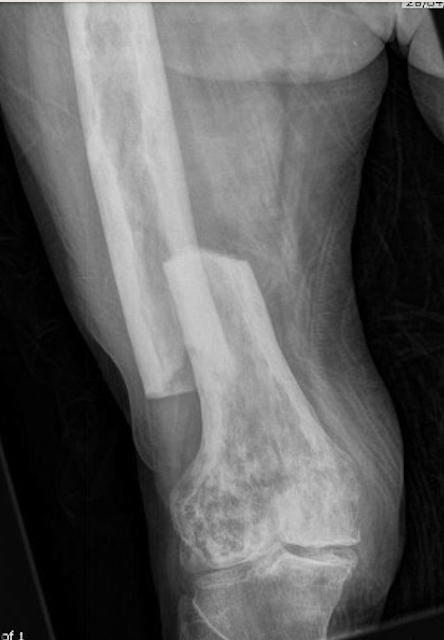

Femur

Tibia

Tibia deformity - sabre tibia

Fracture

Issues

Paget's fractures likely have normal healing capacity

Hard bone - difficult entry points

Bleeding

Deformity - may require osteotomy prior to IM nails